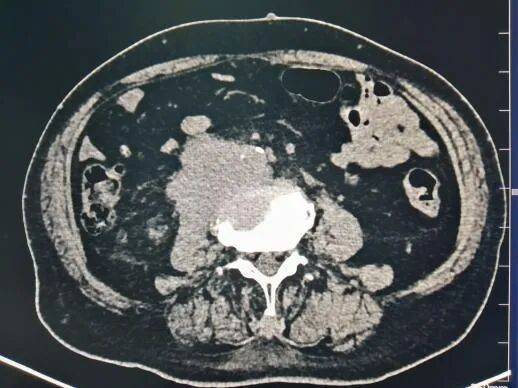

腹膜后脂肪肉瘤(位于右肾旁前间隙,肾脏及肾周脂肪受压向后内侧移位,升结肠和胰头受压向前内侧移位)。肿瘤以实性成分为主,内部及边缘部可见脂肪低密度影